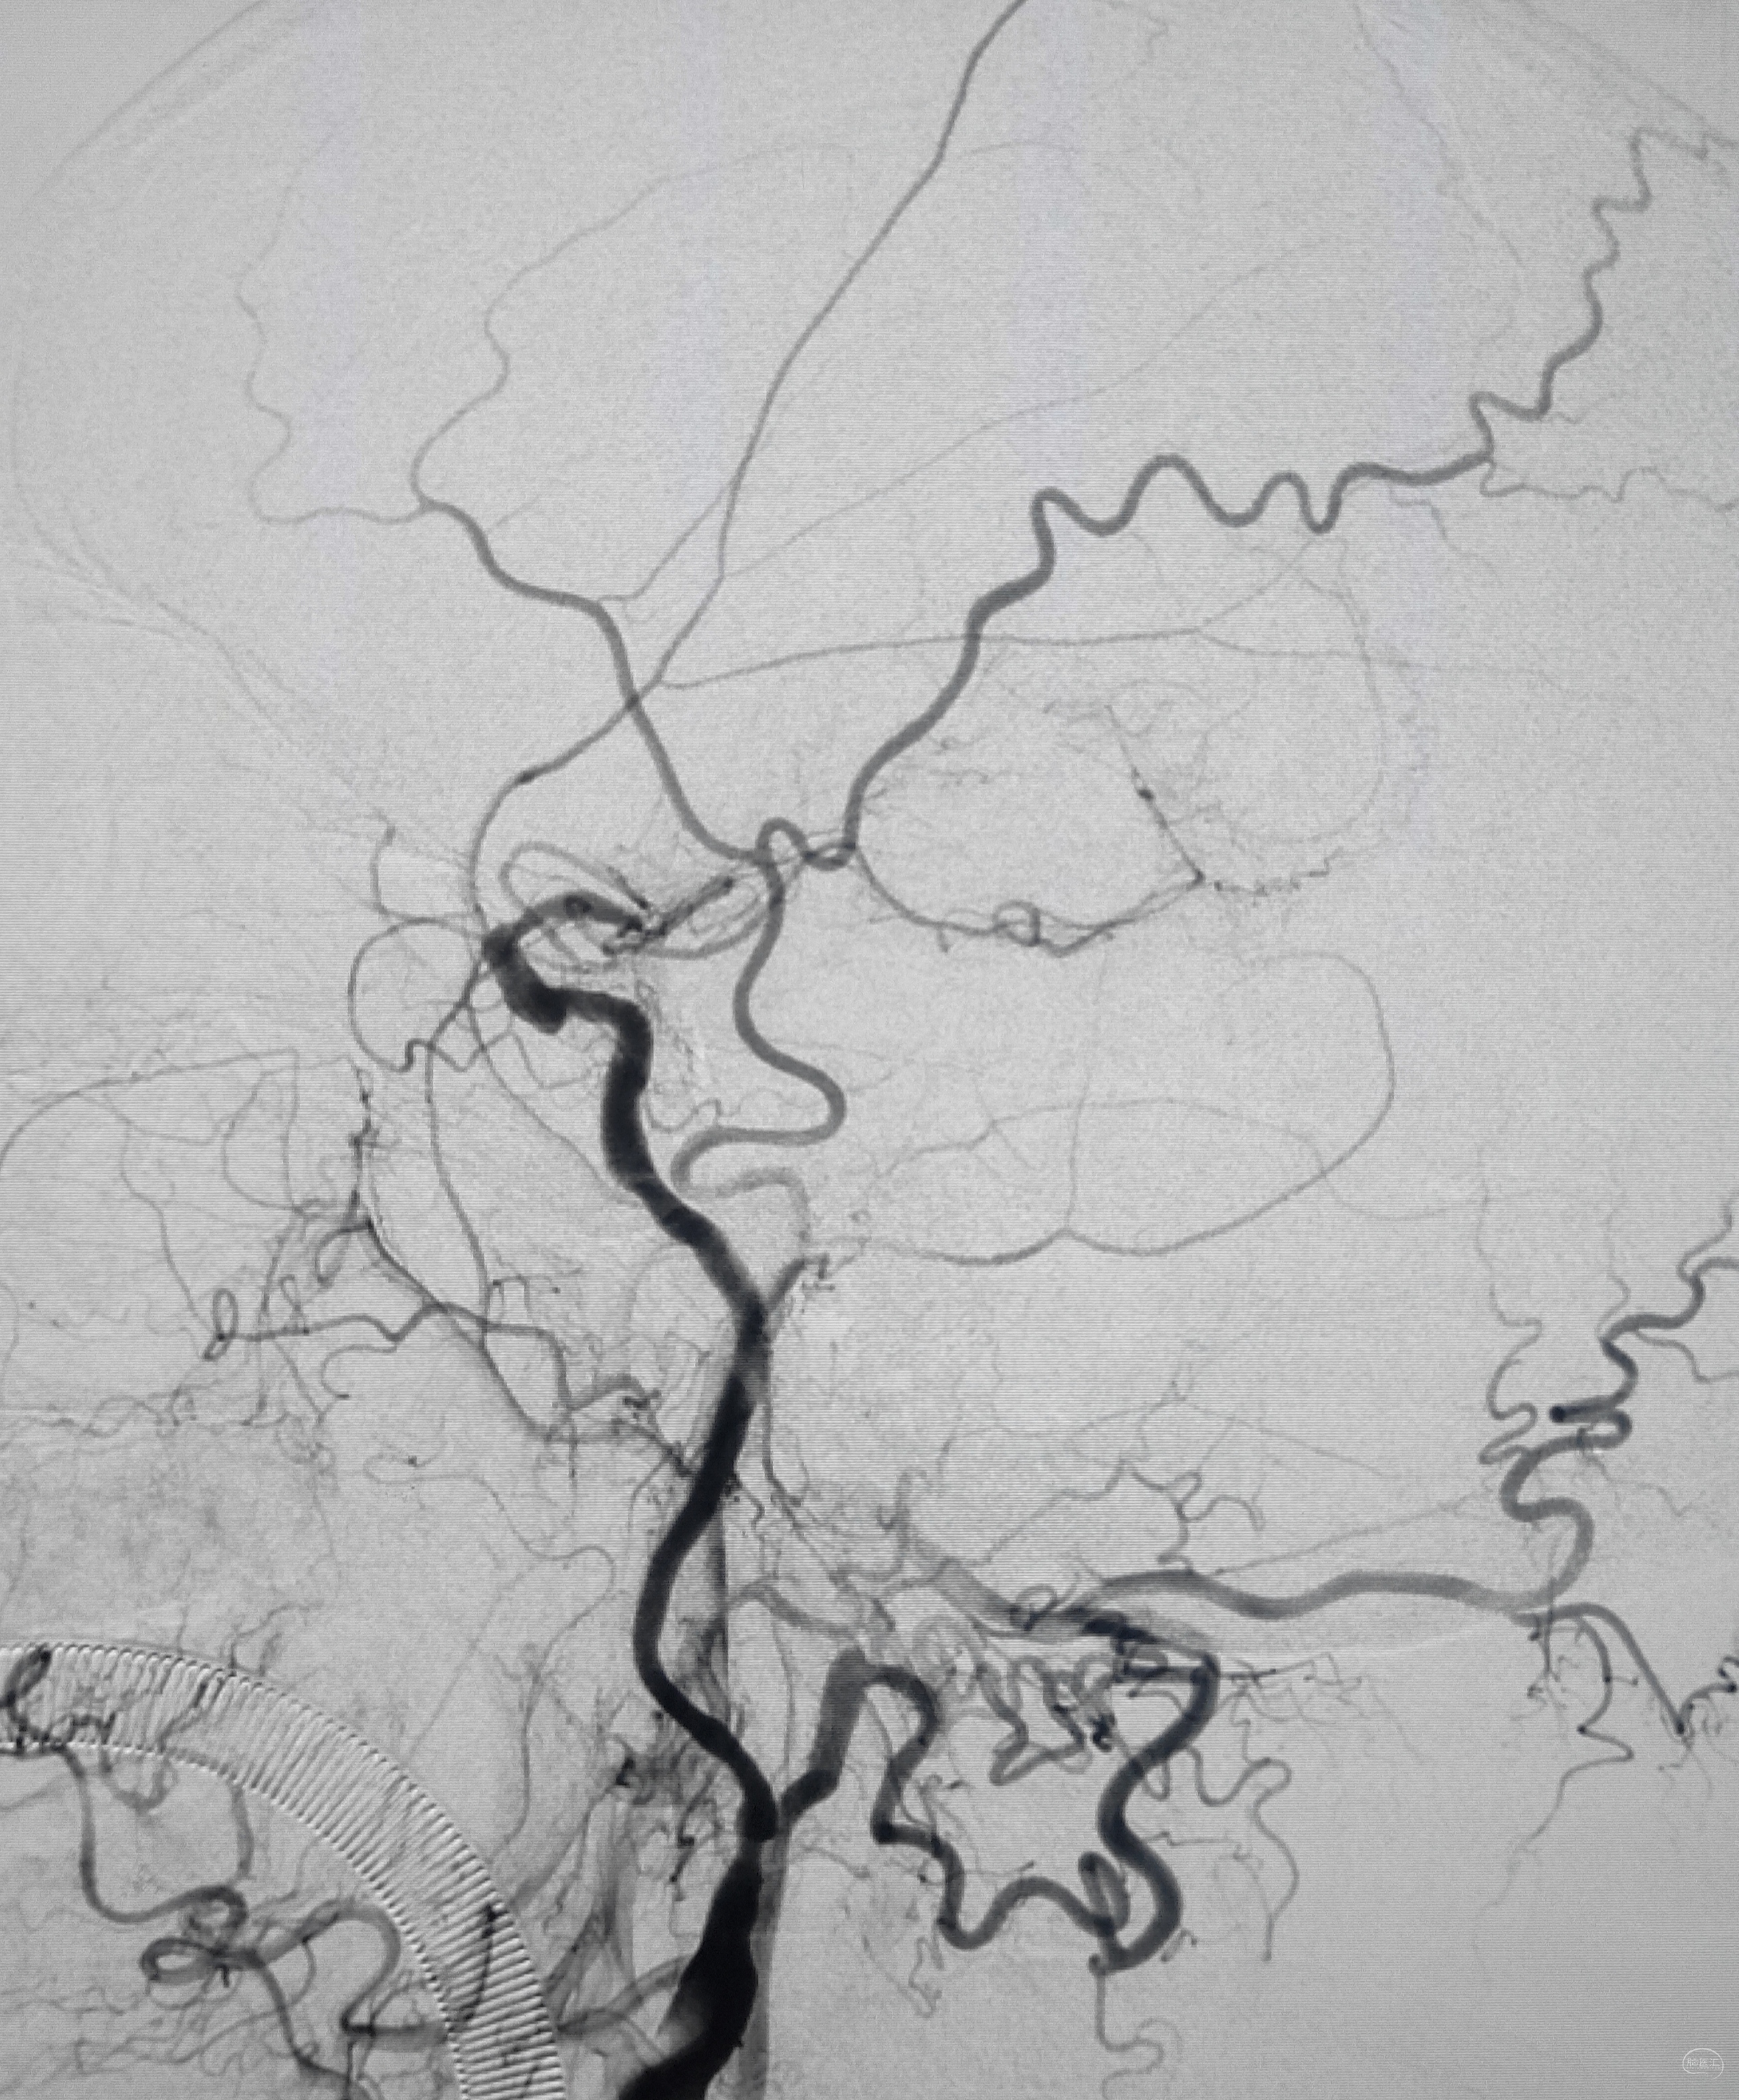

如约初诊:女儿彬彬有礼,父亲中年男性,52y,间断头晕不适多年,口服药物效果不佳,遂在外院做了脑血管造影,推荐过来做脑血管搭桥。调取DSA影像后感觉血管比口述的情况复杂,远不是搭桥能够解决问题,毕竟是“头晕”为主诉,下面结合图像,分述如下:

弓上造影初见:问题(一)左侧锁骨下动脉闭塞,主诉为头晕,双上肢收缩压差>20mmHg,这就是祸根?接着看弓上造影晚期像。

弓上造影晚期:剂量因素,逆流盗血隐隐可见,复合预期,那就看看对侧椎动脉情况吧

右侧锁骨下造影:右侧椎动脉开口也是重度狭窄,血流速度缓慢,闸门效应明显,此刻,不禁感叹血管的伟大,自己都狭窄得不要不要的了,还努力给对侧代偿供血,奉献精神佳!

右侧颈总动脉正侧位造影:意料之外的是,枕动脉通过肌支与右侧椎动脉吻合(紫色箭头),像极了《大风吹》的歌词“借一杯天上的水”,源源不断进行着血流的补充。但是好景不长,同侧V4段明显狭窄,无情的设置了第二道坎(绿色箭头)。

左侧颈总动脉造影:颅内床突段以远基本闭塞,仅残涓涓细流,血供极差,脑膜中动脉瘤仅少量代偿,确实不容易,这估计就是想来搭桥的初衷了吧。